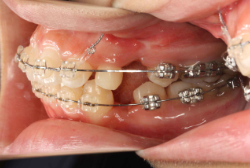

牽引(埋伏犬歯を牽引した症例)

埋伏歯とは、骨または歯茎の下に埋まって出てこない状態の歯のことを言います。埋伏歯があると歯が押されて歯並びが悪くなってしまったり、永久歯が生えてこれない原因になる恐れがあります。

「乳歯が生え替わらない」という主訴で来院したケースです。 診断の結果、「左上永久犬歯が第一小臼歯後方上部に埋伏しているため、左上乳犬歯が晩期残存している症例」と判明しました。

このような症状の場合は、手術で埋伏している永久歯に金具を取り付け、矯正装置で牽引する必要があります。同時に凸凹の解消と前突した前歯を内側に入れるために上下左右の小臼歯を抜歯させて頂くことといたしました。

この方の場合は、マルチブラケット装置にて治療を開始し、治療期間2年3ヶ月で終了しました。犬歯の牽引距離が非常に大きかったため当院の平均治療期間よりも大幅に期間がかかりましたが、埋伏犬歯を完全に正しい位置まで誘導することができました。同時に 前歯の前突と配列の凸凹も解消しました。

このような症例は、成人してしまうと埋伏歯の反応性が悪く、あまりにも動きが悪い場合は牽引をあきらめて抜歯する場合もあります。歯科医院の検診で親知らず以外の埋伏歯を指摘された場合は、できるだけ早く矯正専門医に御相談下さい。